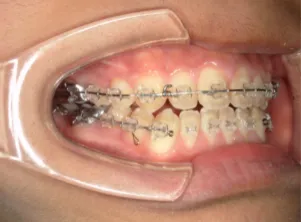

治療中④中2:マルチブラケット法へ移行:上下正中を合わせたい

*マルチブラケット法